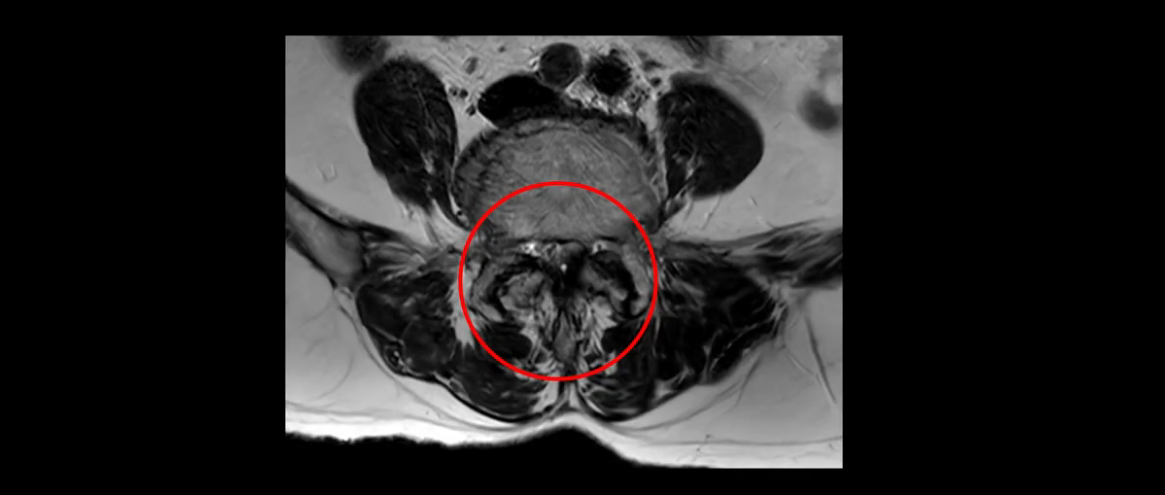

4번 5번에는 뼈가 밀려 나간 전방전위증도 있고,

또 척추관협착도 매우 심합니다.

척추관이 심하게 좁아져 있습니다.

이렇게 여러 마디가 안 좋고 뼈도 밀려 나가 있으니까 나사박는 수술해야 하는데, 대학병원에서도 수술을 한 번에 못 하고 두 번에 나눠서 해야 한다고 들으셨습니다. 왼쪽으로 신경가지가 빠져나가는 추간공도 많이 좁아져 있습니다.

이렇게 신경 구멍들이 좁아져 있고 신경이 눌리니까 엉덩이와 다리가 너무 저리고 아파서 아예 일어서질 못하니까 휠체어를 타고 병원에 내원하셨는데요. 그럼 어떻게 이분처럼 신경이 눌려있는 환자분들을 수술 없이 치료해서 잘 걷게 만들고 엉덩이와 다리가 저리고 아픈 증상이 사라지게 할까요? 지금부터 설명해 드립니다.